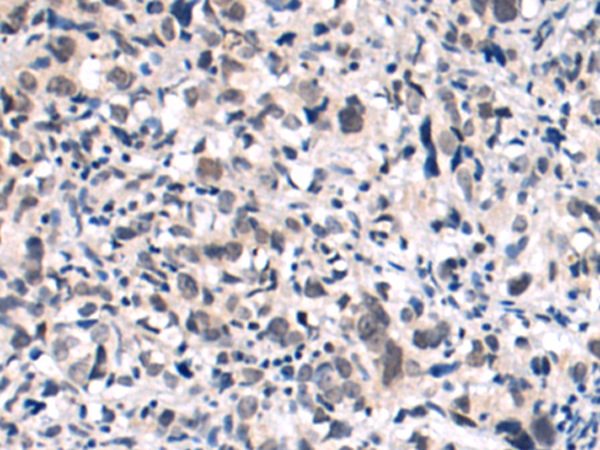

分类: 科研抗体货号: P02037别名: XRG6; C8orf5; C8orf7; C8orf21应用: IHC反应种属: Human, Mouse, Rat